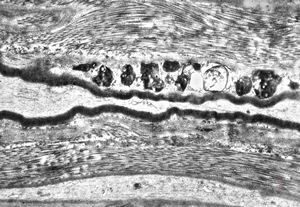

F,12y. | hypertrophic (onion bulb) neuropathy - n.suralis

F,31y. | demyelinating hypertrophic neuropathy - n. suralis- bands of Büngner with collagen-filled pockets

M,13y. | - n.suralis - hypertrophic demyelinizing neuropathy